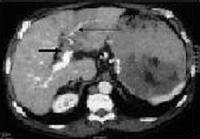

Foto 9: Carcinom hepatocelular grefat pe o ciroya hepatica de etiologie alcoolica, complicat cu tromboza de vena porta (sageata scurta trombul cu o intrerupere brusca a traiectului portei, sageata lunga indica dezvoltarea circulatiei compensatorii). |